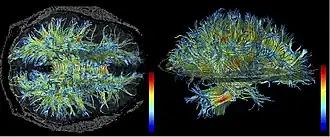

High resolution data acquired on 3-Tesla magnet and post-processed using automated tracking procedure.

High resolution data acquired on 3-Tesla magnet and post-processed using automated tracking procedure. -